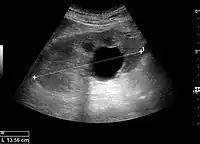

Masses are seen as a distortion of the normal renal architecture. Most renal masses are simple cortical renal cysts with a round appearance and a smooth thin capsule encompassing anechoic fluid. The incidence increases with age, as at least 50% of people above the age of 50 have a simple cyst in one of the kidneys. Cysts cause posterior enhancement as a consequence of reduced attenuation of the ultrasound within the cyst fluid (Figure 5). The simple cyst is a benign lesion, which does not require further evaluation.[1]

Figure 5. Simple renal cyst with posterior enhancement in an adult kidney. Measurement of kidney length on the US image is illustrated by '+' and a dashed line.[1]